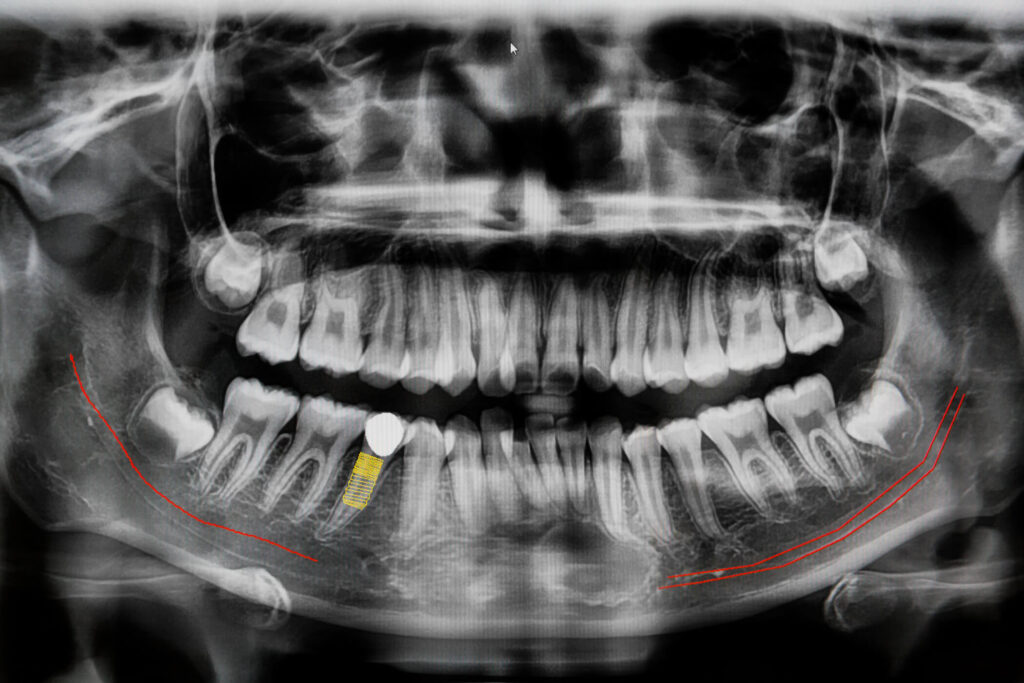

To determine whether we are dealing with periodontal disease or gingivitis, we perform an X-ray and a probing test. This will tell us if there is bleeding, the depth of the cavity in the gums and if there is bone loss.